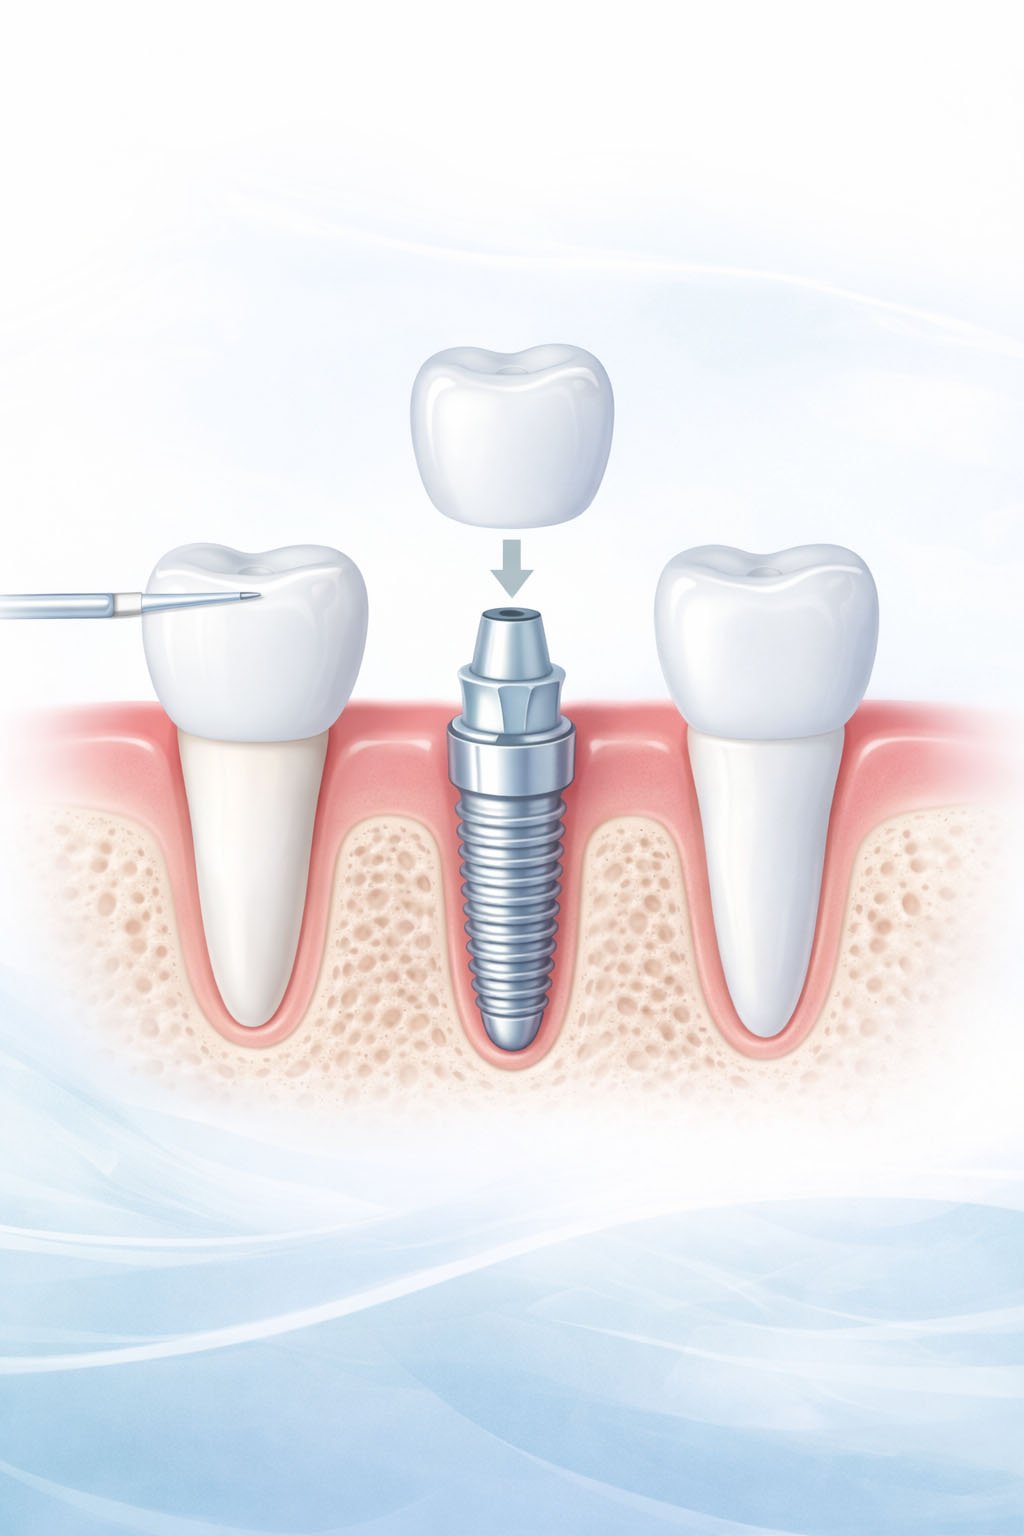

Dental Implants

Immediate Loading Implants

Zirconia Crowns & Bridges